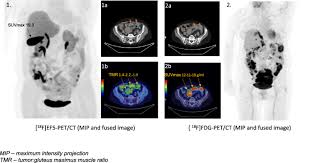

Hyperreactio Luteinalis Mimicking Malignancy During Pregnancy With Elevated Ca 125 Sciencedirect

Hyperreactio Luteinalis Mimicking Malignancy During Pregnancy With Elevated Ca 125 Sciencedirect from ars.els-cdn.com